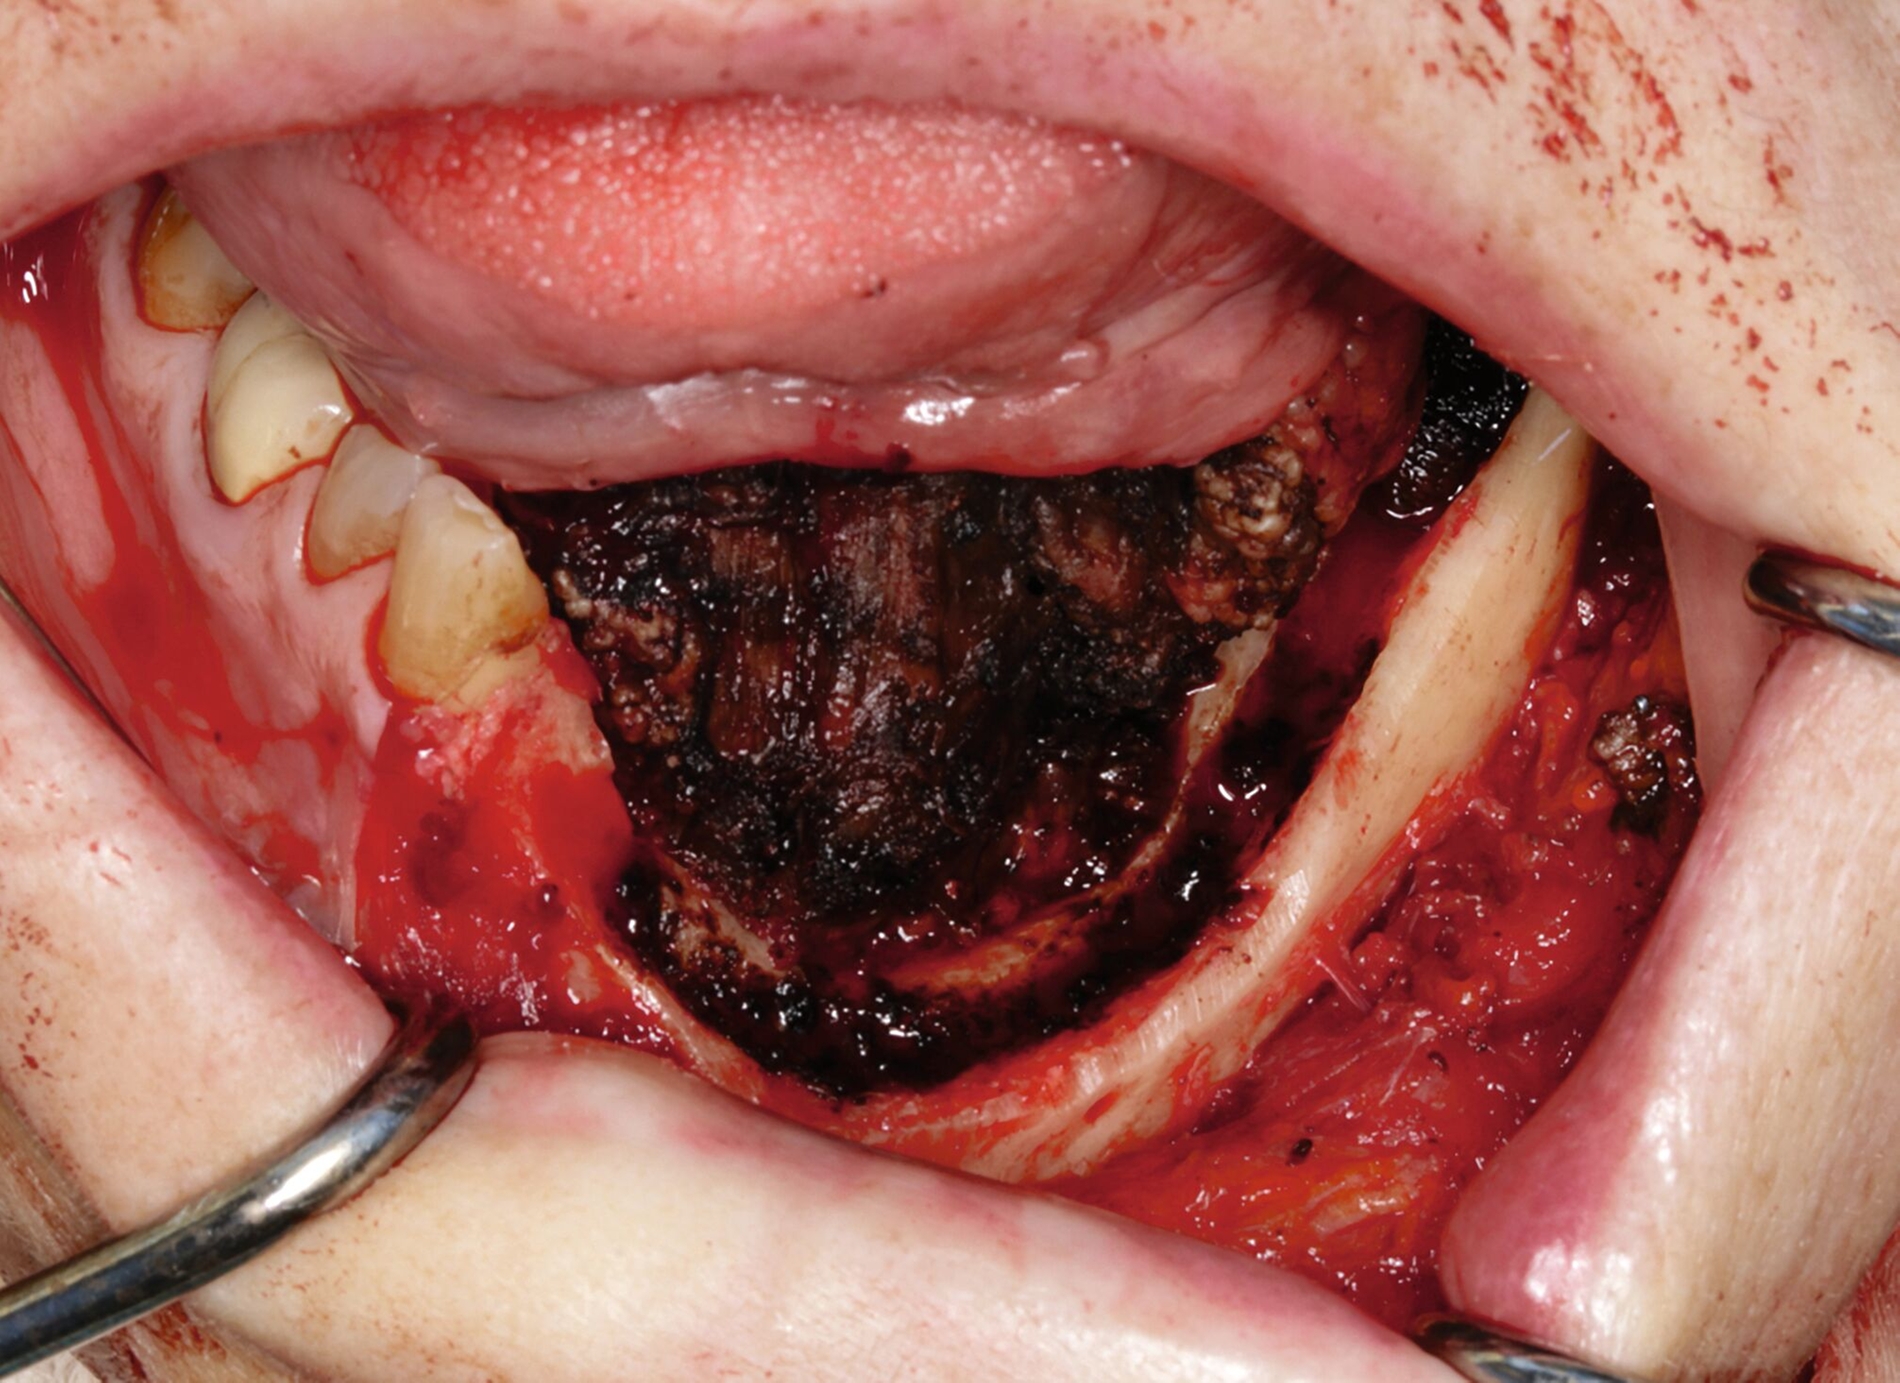

Die prätherapeutische Fallvorstellung im interdisziplinären Hauttumorboard ergab die Empfehlung zur primären Resektion und zu einer Halslymphknotenentfernung der Level I–III beidseits. Diese erfolgte im Sinne einer kontinuitätserhaltenden Unterkieferteilresektion (Abbildungen 4 bis 6). Die Rekonstruktion erfolgte durch ein mikrochirurgisch anastomosiertes, fasziokutanes Radialistransplantat vom linken Unterarm. Der Entnahmedefekt wurde mittels Vollhaut vom linken Unterarm gedeckt. Zudem wurde eine beidseitige selektive Halslymphknotenausräumung in Level IA, IB, IIA, IIB und III durchgeführt. Die Patientin konnte in gutem Allgemeinzustand am 15. postoperativen Tag entlassen werden.